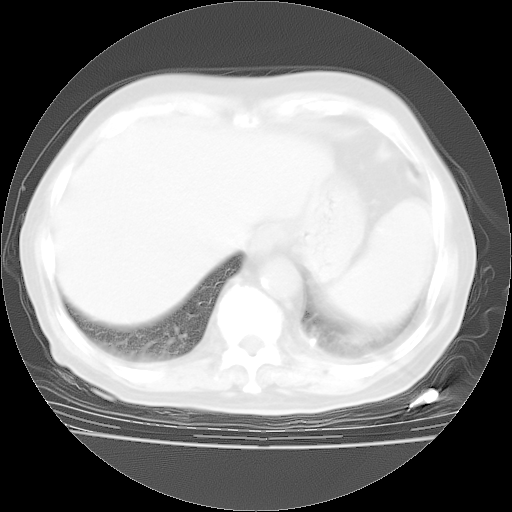

4月28日肺部CT——再次出现类似去年5月9日——透光度降低,“间质性”改变。